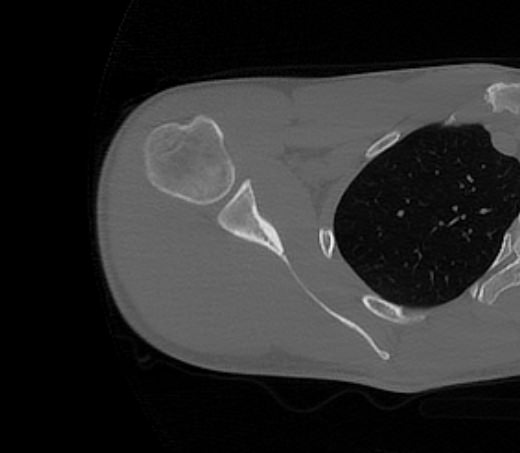

Наиболее информативным методом диагностики патологии плече-лопаточной области является мультиспиральная компьютерная томография. КТ относится к лучевым методам исследования, то есть для получения изображения внутренних органов применяется рентгеновское излучение, которое лучше всего подходит для изучения плотных структур, в частности, костных тканей. В процессе исследования томограф послойно сканирует область лопатки при помощи проникающей способности рентгеновских лучей, затем с помощью компьютерных приложений данные преобразуются в наглядные трехмерные изображения исследуемых органов.

Аппараты сканируют область исследования в течение нескольких секунд, производя одномоментно от 64 до 128 тончайших срезов толщиной от 0,5 мм. Высокая скорость сканирования обеспечивает минимальную дозу облучения для пациента. При этом получаются четкие изображения с высоким контрастным разрешением, что дает возможность рассмотреть исследуемую зону в мельчайших подробностях. Кроме того, томографы создают объемные 3D-изображения области лопатки и прилегающих органов и тканей, что помогает в оценке пространственного соотношения анатомических структур, выявленной патологии и способствует проведению точной диагностики.